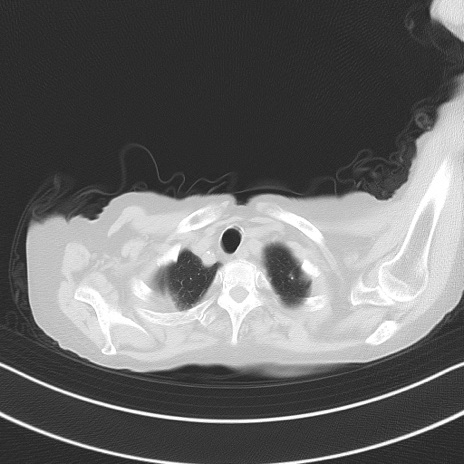

横断像